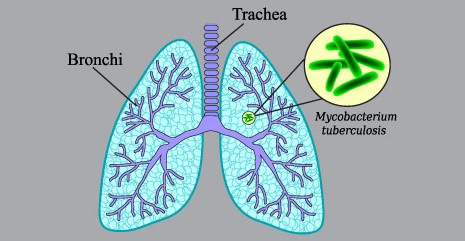

잠복결핵은 결핵균에 감염되어 있지만 증상이 나타나지 않는 상태를 말합니다. 이런 사람들은 일반적으로 감염의 초기 단계에서 결핵 질환을 전파하지 않으며, 결핵이 활성화되기 전까지 아무 증상없는 상태를 유지합니다.

이는 마치 결핵균이 "잠자고 있는" 상태와 비슷하다고 볼 수 있으며, 이 때문에 이를 '잠복 결핵'이라고 부릅니다. 약 10%의 잠복 결핵 환자들이 평생 중 어느 시점에서든 결핵으로 질환을 발병하게 됩니다. 그리고 이 비율은 면역 체계가 약화된 사람들, 예를 들면 HIV 감염자나 특정 약물을 복용하는 사람들에서는 훨씬 높아집니다.

잠복결핵 검사는 결핵균의 감염 여부를 진단하기 위한 검사입니다. 이 검사는 전염되지 않는 잠복결핵 상태를 확인하는데 도움을 줍니다. 잠복결핵 검사 방법은 투베르쿨린 피부반응검사(TST)와 인터페론 감마 분비 검사(IGRA)가 일반적으로 사용됩니다.

TST는 결핵균 항원을 팔의 피부에 주사한 뒤 48~72시간 사이에 반응 크기를 측정하여 결핵균 감염을 확인하는 검사입니다. 결과는 피부 반응 크기로 해석되며, 일정 기준 크기 이상이면 양성 판정을 받을 수 있습니다. IGRA는 결핵균에 노출된 후 면역 시스템이 발현하는 특정 혈액생물학적 반응을 측정하는 검사입니다. 이 검사는 혈액을 채취하여 결핵균 항원에 대한 인터페론 감마 분비를 측정하고, 이를 통해 결핵 감염 여부를 확인합니다.